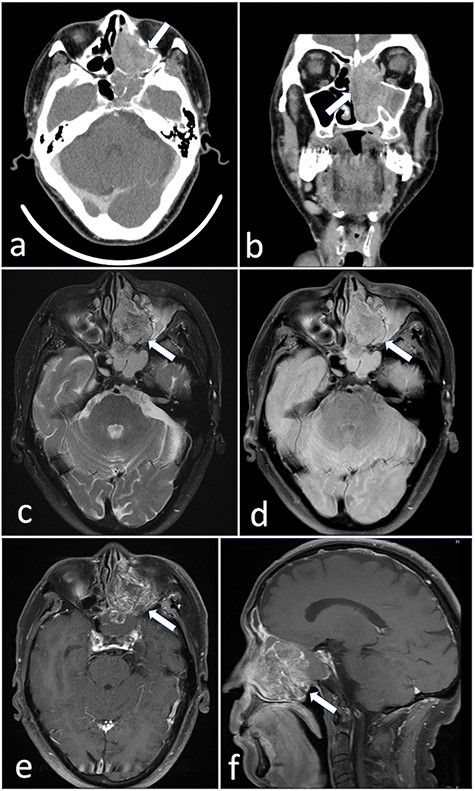

A 72-year-old man was referred to our hospital with complaints of left facial pain and nasal obstruction. Upon physical examination, a mass lesion was found in the left nasal cavity. Computed tomography (CT) revealed a tumor 5.5 cm in size in the left nasal cavity (Fig. 1a and b). Magnetic resonance imaging revealed a tumor 5.5 × 4 × 3 cm in size in the left ethmoidal sinus and left nasal cavity, with invasion of the left orbital cavity, left maxillary sinus and intracranial cavity (Fig. 1c–f). A tumor biopsy was performed. Histopathologically, atypical cells with eosinophilic cytoplasm proliferating as solid nests were apparent (Fig. 2a and b). Massive necrosis was also seen. Immunohistochemistry was performed using the Dako Envision+ system with dextran polymers conjugated to horseradish peroxidase (Dako, Glostrup, Denmark). The following primary antibodies were used: CDX-2 (DAK-CDX2, Dako), chromogranin A (polyclonal, Abcam, Cambridge, England), cytokeratin (AE1/AE3, Dako), desmin (D33, Dako), NCAM (123C3, Dako), NUT (polyclonal, Abcam), p16 (E6H4, Roche, Basel, Switzerland), p53 (DO7, Dako), p63 (DAK-p63, Dako), SALL4 (6E3, Sigma-Aldrich, St Louis, MO, USA), SMARCA4 (polyclonal, Proteintech, Rosemont, IL, USA), SMARCB1 (polyclonal, Bethyl Laboratories, Montgomery, TX, USA), Sox-2 (D1C7J, Cell Signaling Technology, Danvers, MA, USA), synaptophysin (DAK-SYNAP, Dako) and S-100 (polyclonal, Dako). The tumor cells were positive for cytokeratin AE1/AE3 (Fig. 2c) and p63 (Fig. 2d) but negative for S-100, NCAM, synaptophysin and chromogranin A. The tumor was diagnosed as poorly differentiated carcinoma of the paranasal sinuses at first time.

(a and b) CT revealed a tumor 5.5 cm in size in the left nasal cavity (arrow). (c–f) Magnetic resonance imaging revealed a tumor 5.5 × 4 × 3 cm in size occupying the left ethmoidal sinus and left nasal cavity, with invasion of the left orbital cavity, left maxillary sinus and intracranial cavity (arrow).